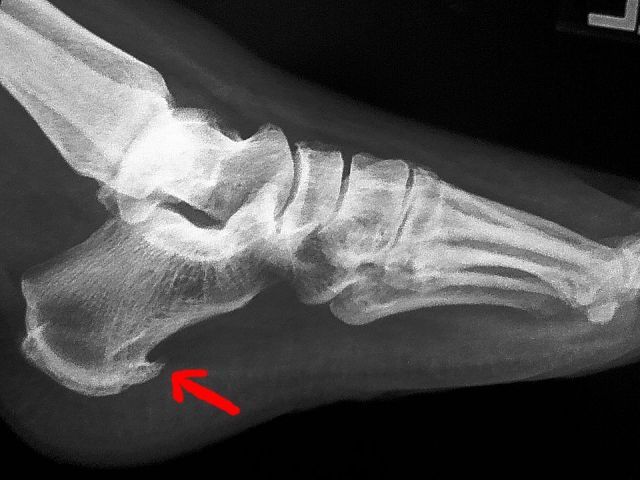

最近一段时间,王老先生双侧足跟持续疼痛。开始时他没当回事,谁知越来越严重,到医院拍片后,发现一侧有骨刺,另一侧也有骨刺

骨刺是由于构成关节的软骨、椎间盘、韧带等软策划变性、退化,关节边缘形成骨刺。就像自行车需要有一个支架才能放稳一样,当骨骼周围的肌肉韧带没办法提供足够的支撑的时候,骨骼的正常受力就会改变,为了不被压断,骨头会自行加固,逐渐长出一个支撑点来保持稳定。

随着年龄增加,每个人或多或少都会有长骨刺的情形,而X光上出现骨刺也不见得就需要接受治疗,只有在骨刺压迫到神经引起其他症状时,才需要进一步接受治疗。